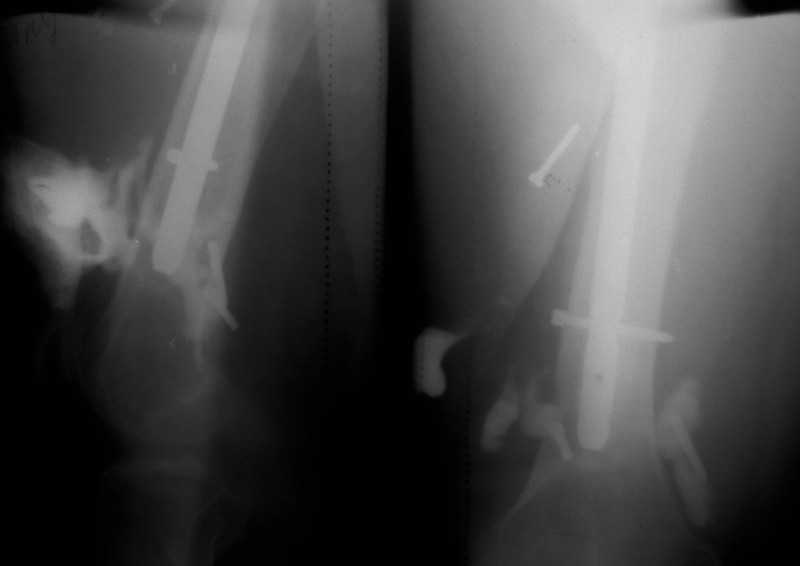

Здравствуйте уважаемые коллеги, прошу Вашего мнения относительно тактики лечения пациента М. 37 лет, рост 170 см. вес 140 кг. Анамнез: пострадал в рез. ДТП в 2004 году, лечился в одной из районных больниц гдебыл прооперирован DCP. в 2006 году перелом м/фиксатора с последующим реостеосинтезом стержнем Кюнчера без блокирования. в 2007 году перелом фиксатора после чего обратился в нашу клинику, где было произведено удаление гвоздя, БИОС L-360 mm D-12 mm с кортико-спонгиозной пластикой, в теч. 6-и мес. больной был под наблюдением динамизация ч-з 2 мес. после чего пациент исчез с поля зрения. Появился с жалобами на болезненность в месте перелома, укорочение ноги, в течении года поочередно в ягодичной области и н/3 бедра функционирующие свищи. На данный момент имеем свищ в н\3 бедра, укорочение ноги на 3 см, внешняя ротация.Произведена фистулография, взят посев из свищевого хода. Планируется: - Удаление м\фиксатора и всех винтов(за исключением проксимального) - I&D с рассверливанием до 16 мм. - кортикотомия, открытое устранение деформаций - БИОС стержнем L-360 mm D-12 mm с а.б. покрытием - бусы с ванкомицином в области свищей

Уважаемый Илья! Если я правильно понял, фистулография у Вас - вторая картинка, а ранки на первой фотографии в области нижних блокирующих винтов и приблизительно на уровне псевдоартроза. Хотелось бы уточнить, есть ли клинические проявления свища на уровне псевдоартроза, отделяемое и т. д. Это существенно влияет на план операции - если перелом неинфицирован,а инфекция только на уровне нижних блокирующих винтов, достаточно удалить конструкции, те, что доступны, не стоит гоняться за кончиками винтов, произвести остеосинтез по Илизарову (на уровне малого вертела стержни, конечно)с п о с т е п е нн о й коррекцией угловой и ротационной деформаций. Параллельно ревизовать место расположения нижнего блокирующего винта, рассверлить, почистить, дренировать.